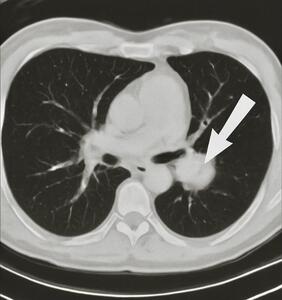

Chest CT revealed a 3 cm left apical pulmonary mass with no apparent lymphadenopathy (Figure 1). The identification of a hypermetabolic left apical lung mass provided a likely source of paraneoplastic antibody production and guided definitive surgical management. PET-CT demonstrated hypermetabolic activity corresponding to the mass (SUVmax 9.5). No distant metastases were identified. The patient underwent left upper lobectomy. Histopathological examination showed sheets of small, round blue cells with high nuclear-to-cytoplasmic ratio, finely granular chromatin, nuclear molding, and numerous mitotic figures, consistent with small-cell lung carcinoma (Figure 2). Immunohistochemistry was positive for synaptophysin, chromogranin, and P/Q-type VGCCs, confirming the paraneoplastic etiology of LEMS.